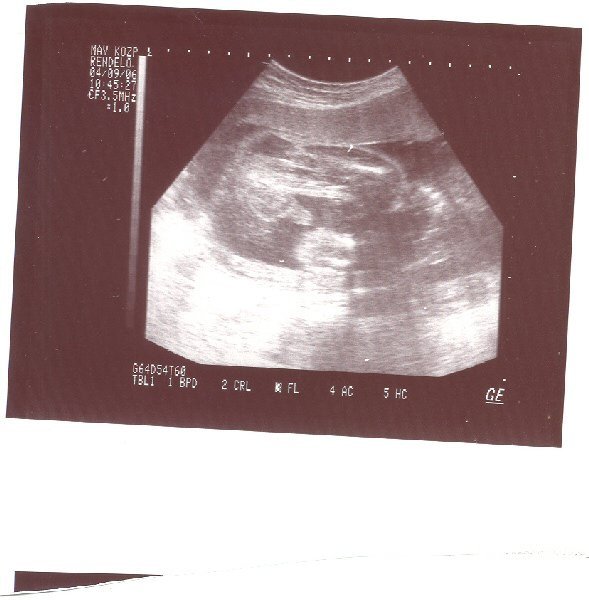

kisfiam 27 hetesen.

kisfiam 27 hetesen.